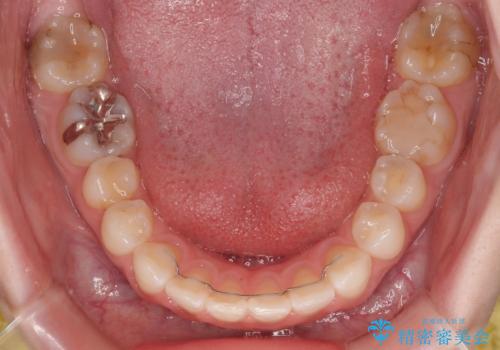

叢生が軽度であったため、僅か半年で装置を除去することができました。